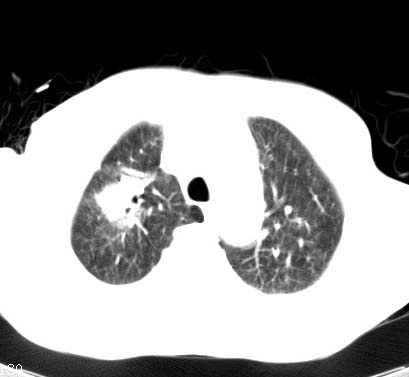

标题: CT14027:男性病人 71岁 咳嗽咳痰数周. [打印本页]

标题: CT14027:男性病人 71岁 咳嗽咳痰数周.

男性病人 71岁 咳嗽咳痰数周.诊断结核应该有保障吧!

右上肺结核,请结合痰检除外活动期;右上叶支气管官腔狭窄建议支气管镜或抗僗后随诊除外堵塞性改变。

高度怀疑肺癌,强烈要求纤支镜检查。

支持双上肺继发性肺结核。